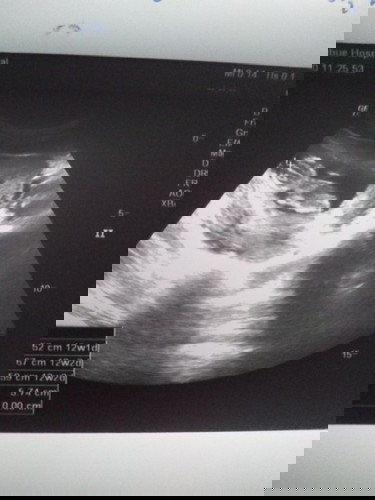

แบบนี้น้องนอนคว่ำหรือว่านอนตะแคงครับ

เดาว่าตะแคงค่ะ 😂 หันหลังใส่เลย